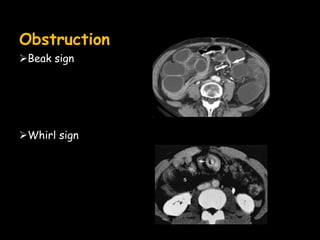

Obstruction

Beak sign

Whirl sign

• #71 Closed loop obstruction;whirl-volvulus